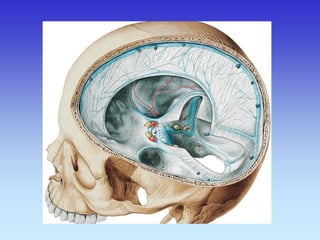

MOŽDANE OVOJNICE

CEREBRPOSPINALNI LIKVOR